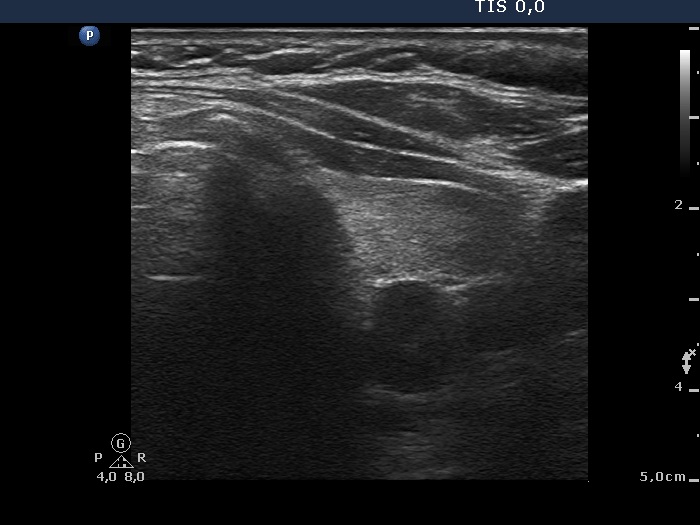

100 consecutive cases of papillary cancer - case 065 (ultrasonographic picture 4)

Middle part of the left lobe, transverse scan. There is a cystic nodule in the dorsal part of the echonormal lobe.